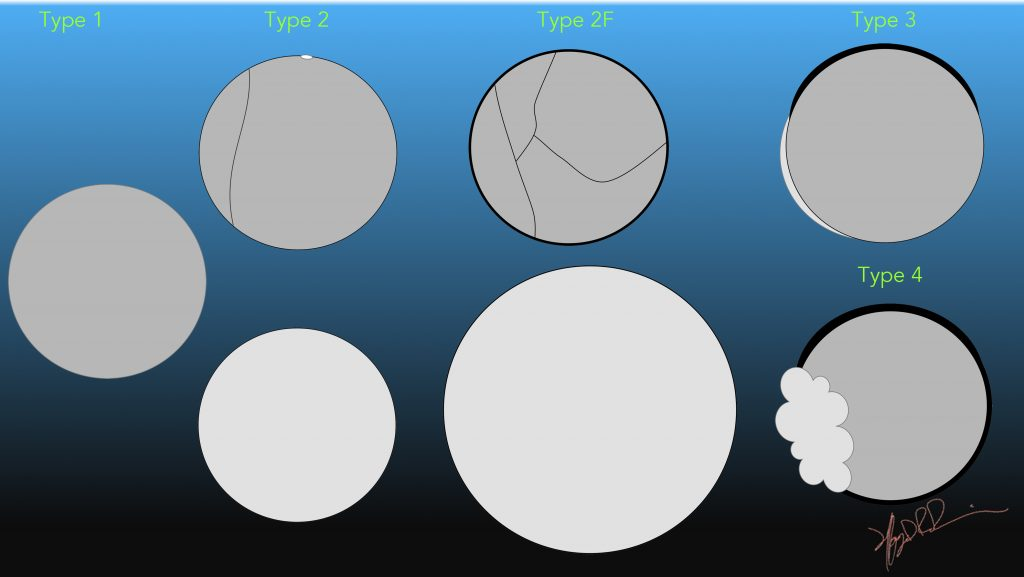

| Bosniak Classification | Description | % Risk of Malignancy |

| I (Benign) | – Benign simple cyst – hairline thin wall – no septa, calcification, solid component – homogeneous attenuation (−10 to 20 HU) – no enhancement | 3.2 |

| II (No further evaluation needed) | Benign minimally complicated cyst – may a few hairline thin septa that may have “perceived”, not measurable enhancement. – Fine calcification or a segment of slightly thickened calcification may be present in the wall or septa. – Also, a well-marginated nonenhancing homogeneous mass < 3 cm with density above simple fluid attenuation (hyperdense cyst). | 6 |

| IIF (Needs follow-up) | Usually benign complicated renal cyst – multiple hairline thin septa or minimal smooth thickening of the wall or septa. – Wall or septa may contain thick and nodular calcification – may have “perceived” but not measurable enhancement. – Also, a well-marginated intrarenal nonenhancing mass > 3 cm with density above simple fluid. | 6.7 |

| III (Indeterminate. Surgical lesion.) | Indeterminate complicated cystic renal mass – thickened irregular walls or septa – measurable enhancement. | 55.1 |

| IV (Clearly malignant. Surgical lesion.) | Malignant cystic renal mass – enhancing soft tissue components (cystic renal cell carcinoma). | 91 |

Source: An update of the Bosniak renal cyst classification system (2005)